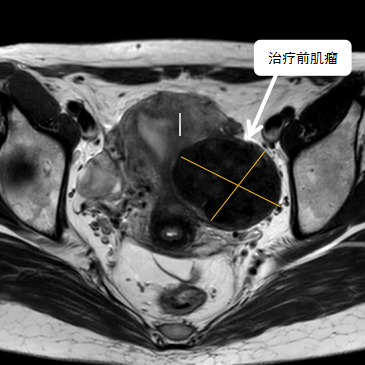

術(shù)前影像資料

經(jīng)過兩個(gè)月的藥物預(yù)處理,完善術(shù)前準(zhǔn)備,治療當(dāng)天陳主任帶領(lǐng)團(tuán)隊(duì)在3.0T磁共振清晰圖像引導(dǎo)下對(duì)子宮肌瘤進(jìn)行精準(zhǔn)消融,患者全程清醒,沒有明顯疼痛,經(jīng)過1個(gè)多小時(shí)的精細(xì)操作,手術(shù)非常成功,消融率接近90%,內(nèi)膜未見損傷!觀察一個(gè)小時(shí)后患者即自行回家。

術(shù)后即刻行增強(qiáng)磁共振檢查,顯示病變被消融近90%,內(nèi)膜未見損傷